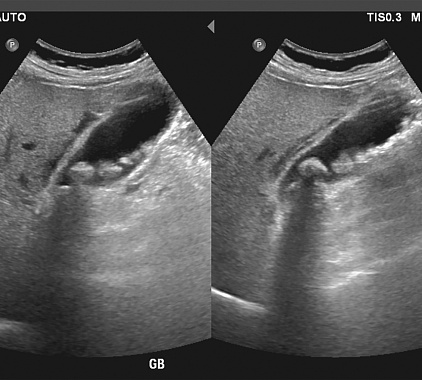

Фотогалерея

Оборудование УЗИ